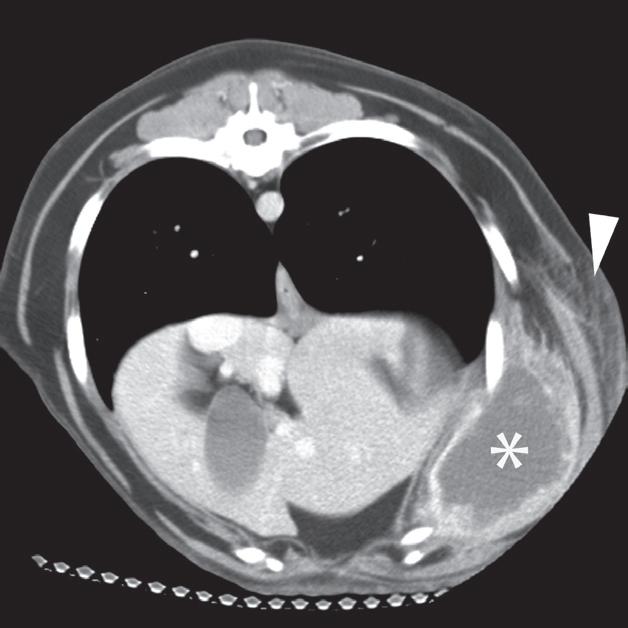

Badanie wykonano u 6-letniego, kastrowanego golden retrievera z fluktującą masą po lewej stronie w dobrzusznej części ściany klatki piersiowej. Radiogram grzbietowo-brzuszny (DV) klatki piersiowej uwidocznił dużą masę miękkotkankową wystającą z lewej ściany klatki piersiowej (a). Duża, jajowata masa jest widoczna na lewej brzusznej ścianie powłok. Jest ona głęboko położona w stosunku do zewnętrznych mięśni skośnych brzucha i wkracza przyśrodkowo do krawędzi żeber (b, c – gwiazdka). Część centralna ma około 15 HU zarówno na niewzmocnionych, jak i wzmocnionych obrazach TK (b, c), a masa ma gruby, obwodowo wzmacniający się rąbek (c). Widać również objawy bardziej powierzchownego, rozlanego zapalenia tkanki łącznej (cellulitis) (b, c – grot strzałki). Masę usunięto chirurgicznie i potwierdzono, że zawierała materiał ropny